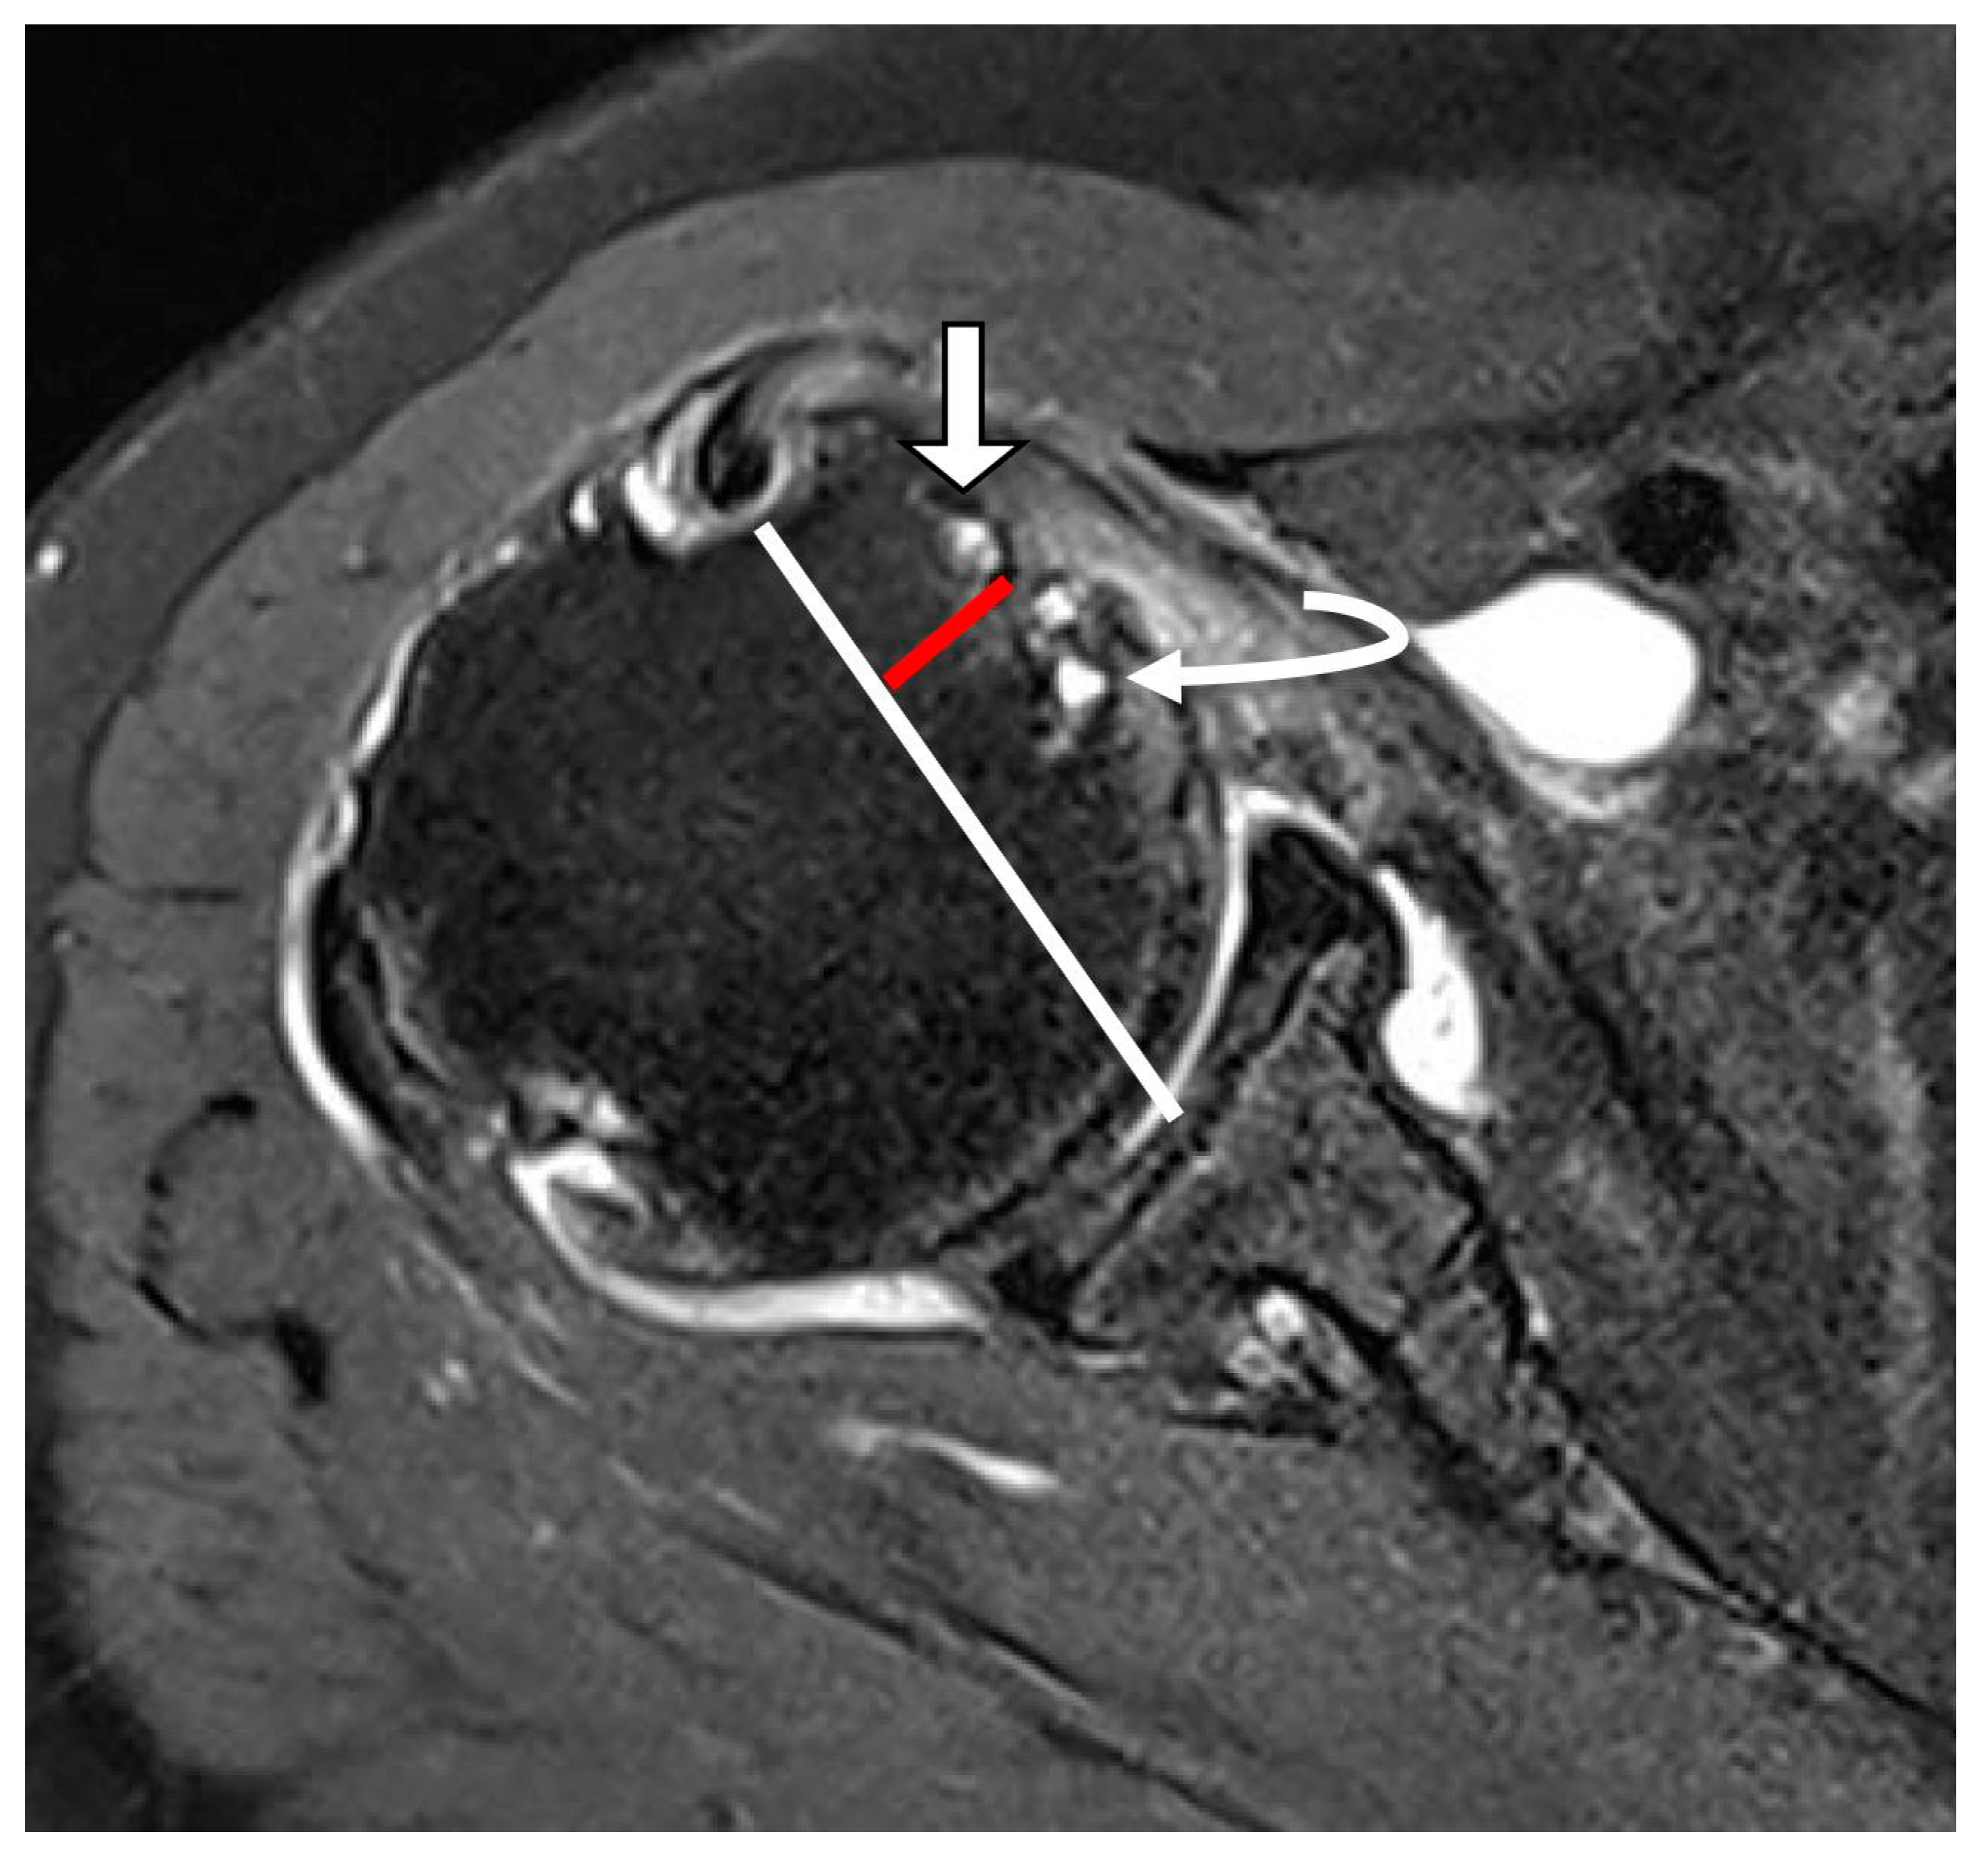

Cysts around the lesser tuberosity were assessed on oblique axial T2-weighted fat-suppressed images, because previous studies have shown that cysts within the lesser tuberosity are highly specific indicators of SSC abnormalities [15,16]. A reference line was drawn from the bicipital groove to the midpoint of the glenoid fossa at the level of the lesser tuberosity. The border of the bony protuberance of the lesser tuberosity was outlined. Only cysts located within the lesser tuberosity were included in the analysis; cysts adjacent to the lesser tuberosity were excluded (Figure 6) [16].

Figure 6.

Cystic lesion in the lesser tuberosity on T2-weighted oblique axial fat-suppressed image. A white line extends from the bicipital groove to the midpoint of the glenoid fossa at the level of the lesser tuberosity. A red line indicates the border of a bony protuberance called the lesser tuberosity. Cysts located within the bony protuberance were defined as cysts within the lesser tuberosity (straight arrow). Cysts adjacent to the bony protuberance were defined as cysts adjacent to the lesser tuberosity (curved arrow).